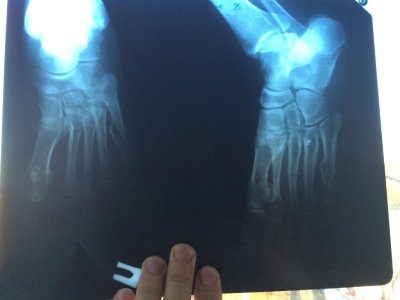

10 марта мама ( 60 лет) сломала 5 плюсневую кость, прилагаю первый снимок и последний, сделанный 30 апреля. Как на ваш взгляд проходит срастание кости? как долго еще носить гипс? можно ли сейчас наступать на ногу?

учитывая массу тела серьезных проблем возникнуть не должно.На первичном рентгеновском снимке есть все показания для оперативного лечения.

Еще раз говорю на снимках очень плохо видно,но кажется начинает формироваться периостальная костная мозоль.Нужно смотреть функцию конечности.Возможно для большего удобства заменить гипс на ортез